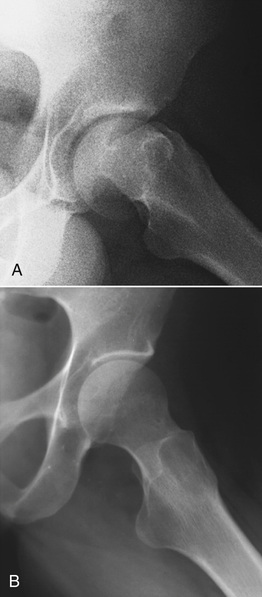

The third general group of factors that affect radiographic quality involve the patient (Box 10-2). These factors are those associated not so much with the positioning of the patient as with the selection of a radiographic technique that properly compensates for the patient's size, shape, and tissue composition. Patient positioning is basically a requirement that is associated with the geometric factors that affect radiographic image quality.

Several of these subject factors are discussed in Chapter 9 in terms of their relation to the attenuation of an x-ray beam. The effect of each on subject contrast is a direct result of differences in attenuation in body tissues.

Given a standard composition, a thick body section attenuates a greater number of x-rays than does a thin body section (Figure 10-31). The same number of x-rays is incident on each section; therefore, the contrast of the incident x-ray beam is zero, that is, there is no contrast.

If the same number of x-rays left each section, the subject contrast would be 1.0. Because more x-rays are transmitted through thin body sections than through thick ones, however, subject contrast is greater than 1. The degree of subject contrast is directly proportional to the relative number of x-rays leaving those sections of the body.

Different sections of the body may have equal thicknesses yet different mass densities. Tissue mass density is an important factor that affects subject contrast. Consider, for example, a radiograph of different salad ingredients (Figure 10-32). These materials have the same thickness and chemical composition. However, they have slightly different mass density from water and therefore will be imaged. The effect of mass density on subject contrast is demonstrated in Figure 10-33.